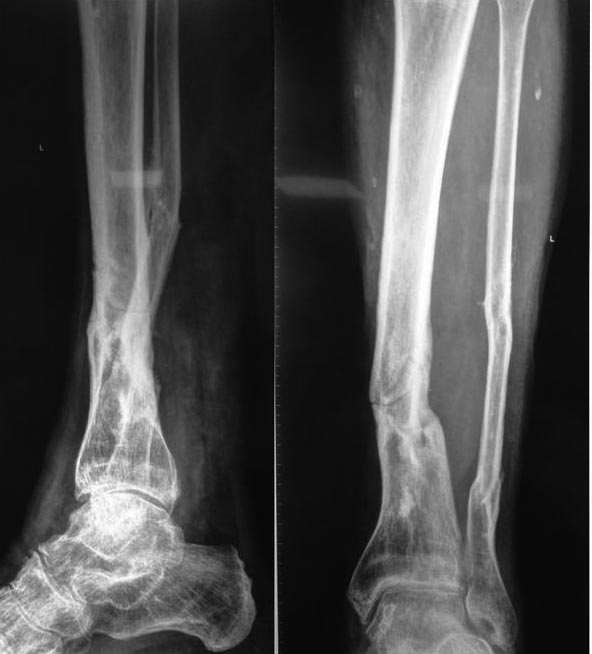

На данный момент ходит самостоятельно с тростью и в ортезе с шинами и замками. Боли нет. Может наступать на ногу и без ортеза - боли также не испытывает. Пальпация в области перелома безболезненна. Последняя рентгенограмма от 22.09.2015 - прослеживается линия перелома.

Здесь сращение сомнительно, а деформация посттравматическая очевидна. Так что, конечно, здесь вполне уместен остеосинтез с коррекцией оси. Аппаратом или внутрикостный - что уж выберете.